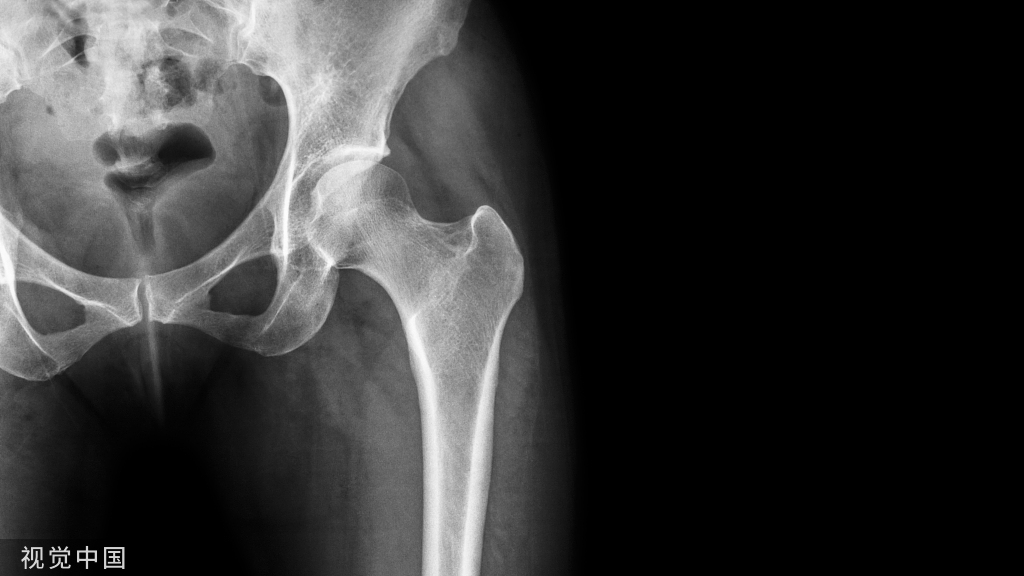

髋关节是多轴的球窝状关节,由股骨的股骨头和髋骨的髋臼两部分组成

髋关节结构—骨

髋关节特点:

1. 头大、窝深

2. 关节囊厚而坚实

3. 关节囊有许多韧带增强

4. 关节囊内有股骨头韧带

运动:球窝关节,又称杵臼关节,能产生屈、伸,展、收,旋内、旋外,环转运动。

股骨头和髋臼的精确对合,结合比较紧密,一系列结构使其难于脱位。

①股骨头:股骨头是髋关节球臼结构中的凸出部分,相当于圆球的三分之二,方向朝上、内、前。有一凹陷,称股骨头凹,有圆韧带附着。股骨头的关节软骨,厚薄不一,中内侧面最厚,周边部最薄。与髋臼相比,股骨头的关节面较大,以便增加髋关节的活动范围。

② 髋臼:由髂骨、坐骨和耻骨三部分组成。中央为髋臼窝,内衬半月形软骨,其下缘由髋臼横韧带连接,使它与股骨头紧密贴合。周围有关节唇,使髋臼变深,以防脱位。髋臼朝前下外方,内下方软骨缺如,形成髋臼切迹,这种解剖结构与股骨头脱位后所处位置有一定关系。

髋臼为髋骨外侧面中部的倒杯形深窝,面向前外、下方为一不完全的半球形窝。关节面为马蹄形或者半月形也称为月状面。上部较宽厚,前后部略窄薄